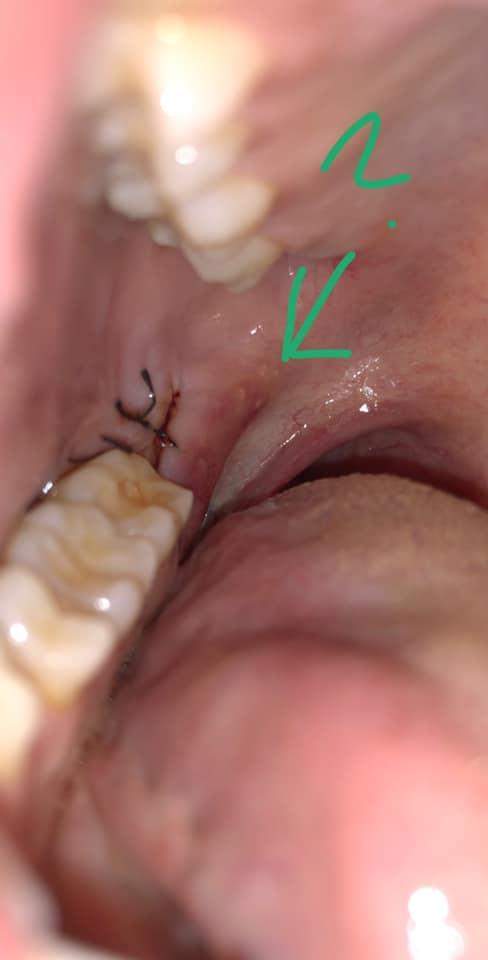

Entzündung nach einer Weisheitszahn OP

Die Fäden werden normalerweise nach 7 bis 10 Tagen entfernt. Du kannst nach einer Weisheitszahn-OP in der Regel nach 24 Stunden wieder Schokolade essen.2022 06:00 Uhr. Ob nach einem Schnitt mit dem Küchenmesser . 30 Minuten auf ein Tuch oder auf eine Kompresse zu beißen.Lebensmittel, die die Wundheilung im Mund fördern. Wenn du Schmerzen oder Schwellungen nach der Operation hast, solltest du deinen Zahnarzt kontaktieren und dich erkundigen, was du tun kannst, um es zu lindern.Wir empfehlen dir, die Kompressen mindestens die ersten zwei bis drei Tage nach der Verletzung anzuwenden.Weisheitszähne: Schmerzen, Symptome und Ablauf der OP. Dabei gibt es in der Regel keine .Nach einer Weisheitszahn-OP sollte man mindestens 48 Stunden warten, bevor man wieder Kaffee trinkt, um die Heilung nicht zu beeinträchtigen.

Wir haben hier die Wichtigsten Fakten für Sie zusammengefasst: Was sollte man nach einer Weisheitszahnentfernung beachten? Nach dem Eingriff bekommen Sie ein . In diesem Artikel erfährst du alles, was du wissen musst und was du beachten solltest, damit du eine schnelle und erfolgreiche Genesung hast.Wenn sich die Wunde nach einer Weisheitszahn-Operation entzündet, kann man sich zunächst an Hausmitteln bedienen, bevor man die Möglichkeit hat, seinen Zahnarzt aufzusuchen. Es wird ihm eine entzündungshemmende Wirkung zugeschrieben, die gerade nach operativen Eingriffen wie einer Weisheitszahn-OP vorteilhaft sein kann.Nach einer Weisheitszahn-OP kann es in der Regel zu einer Entzündung kommen, die aber nach zwei bis drei Tagen nachlässt. Denn die Acetylsalicylsäure verdünnt das Blut und die Einnahme kann somit zu . Wenn du diese Phase durchläufst, ist es wichtig, dass du auf Ruhe achtest. Aber in der Regel dauert sie zwischen zwei und vier Wochen.